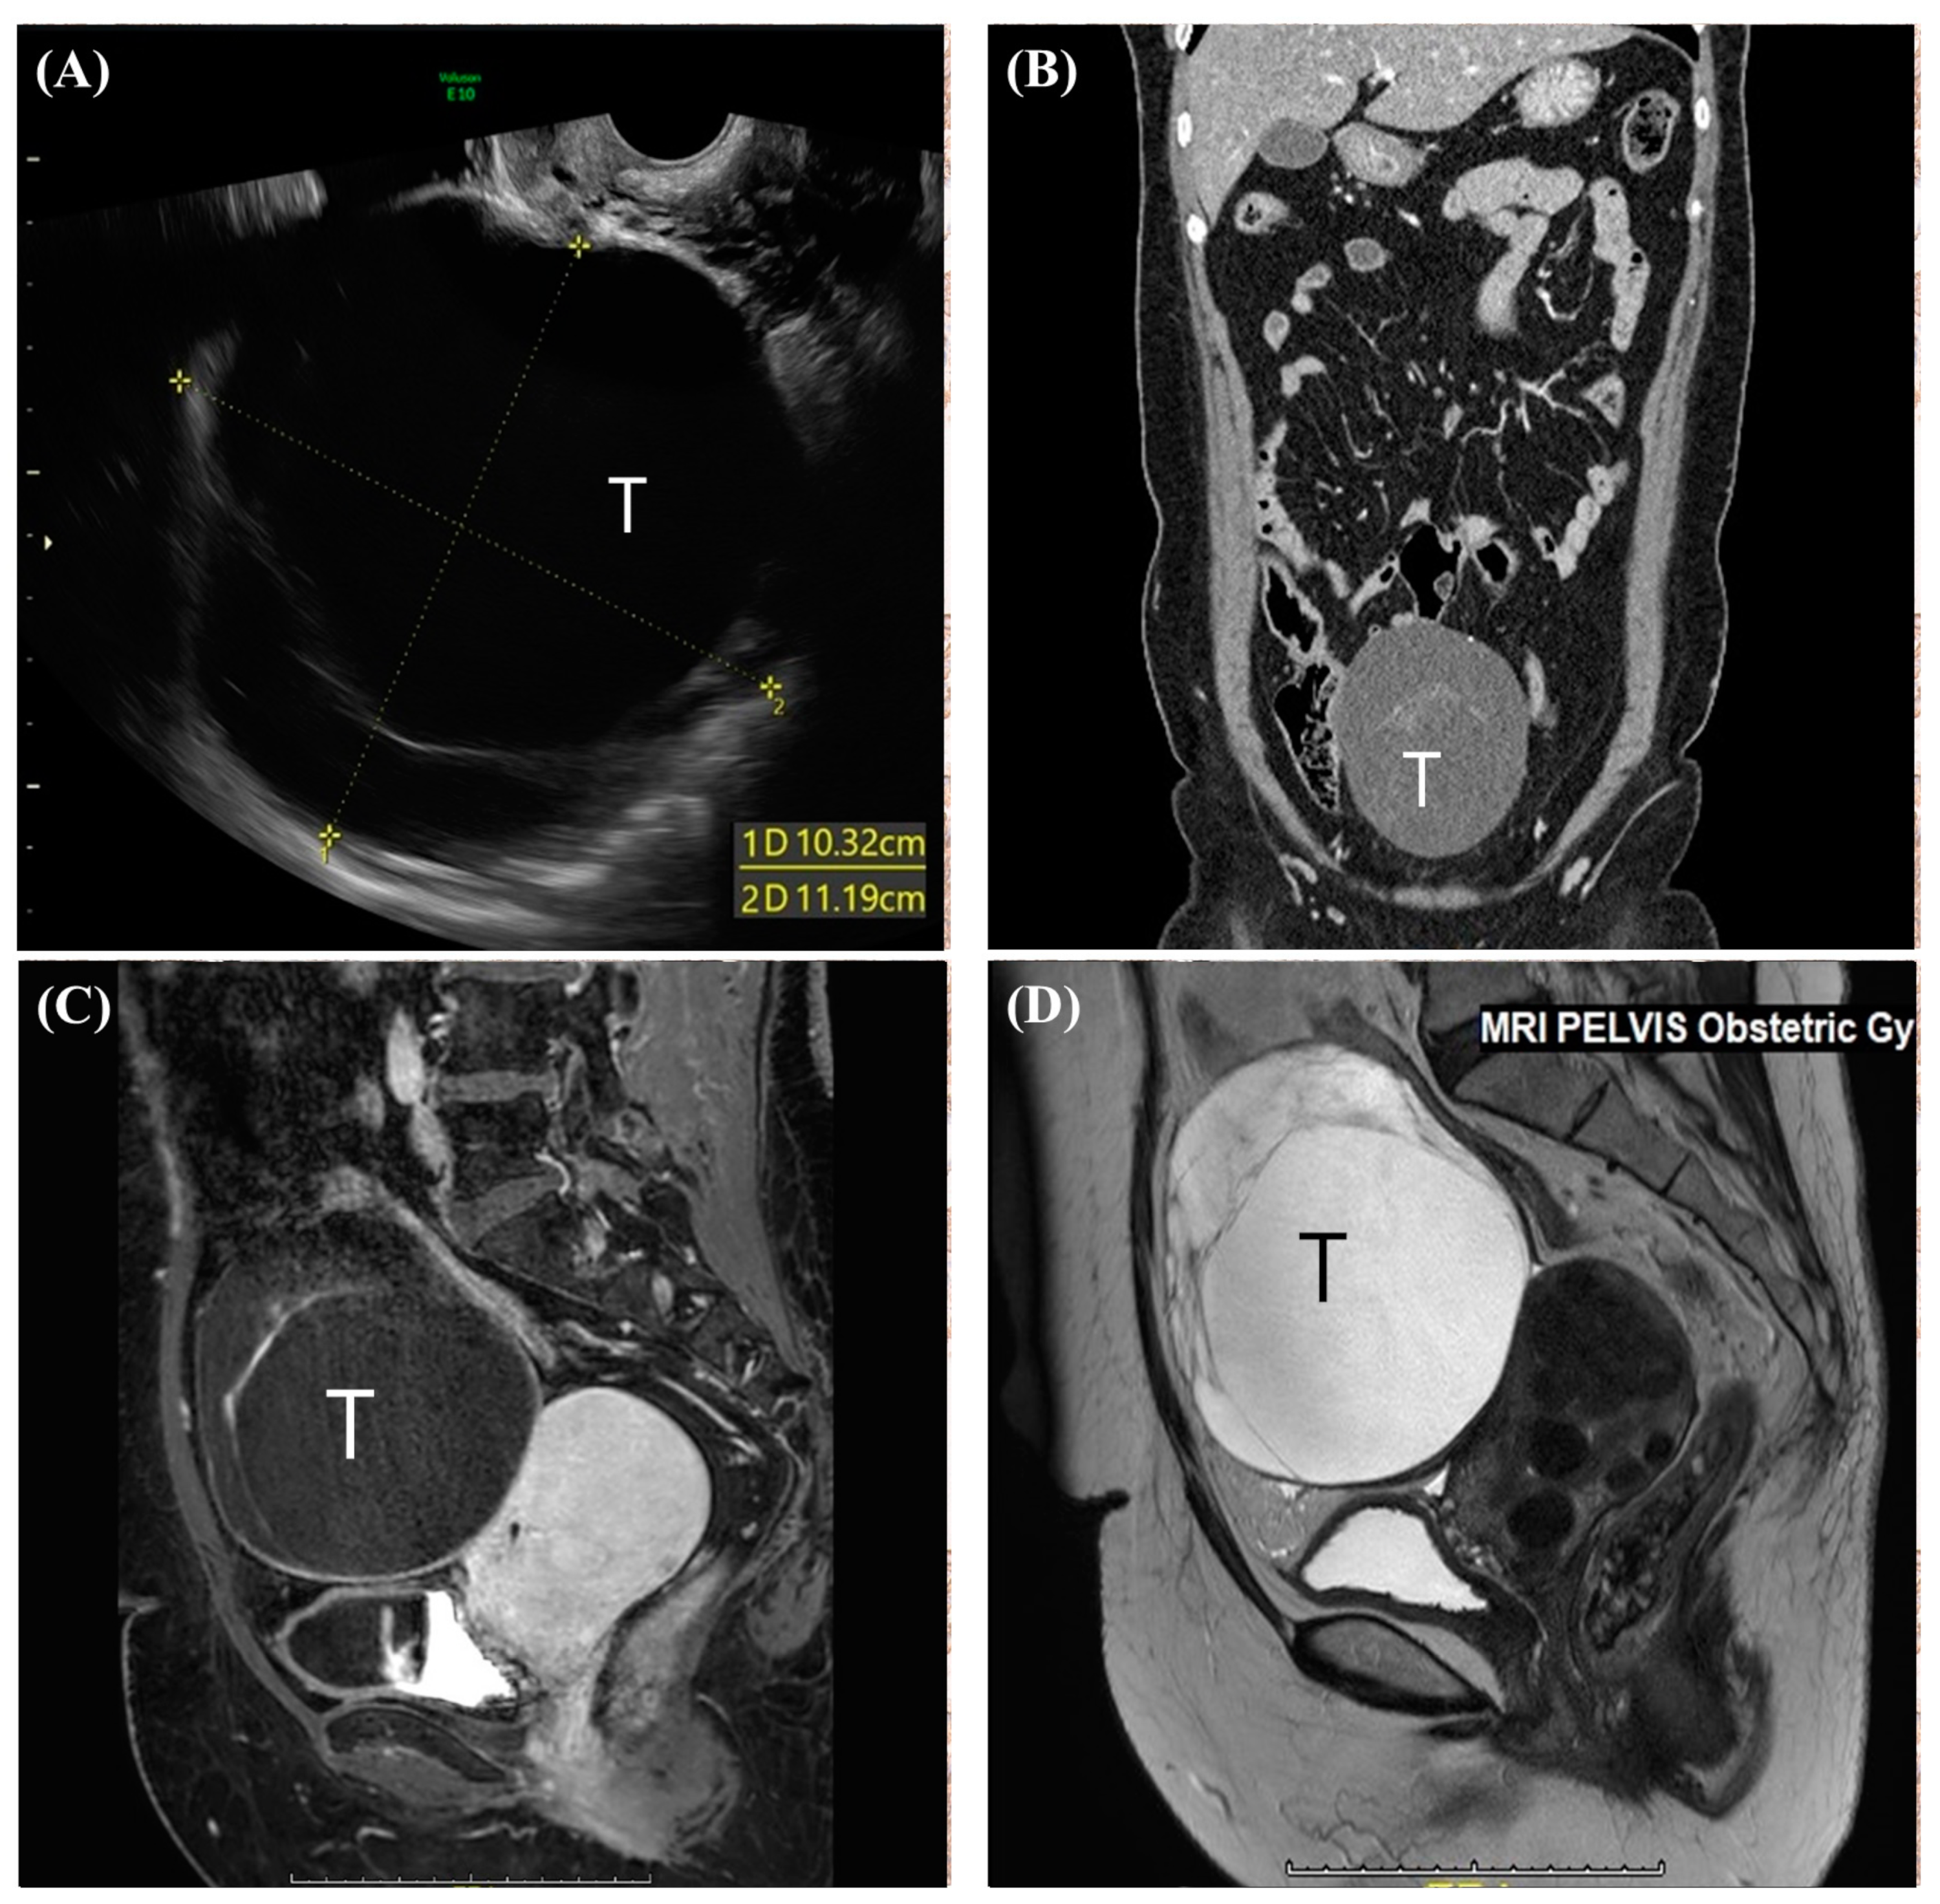

2. Case Report